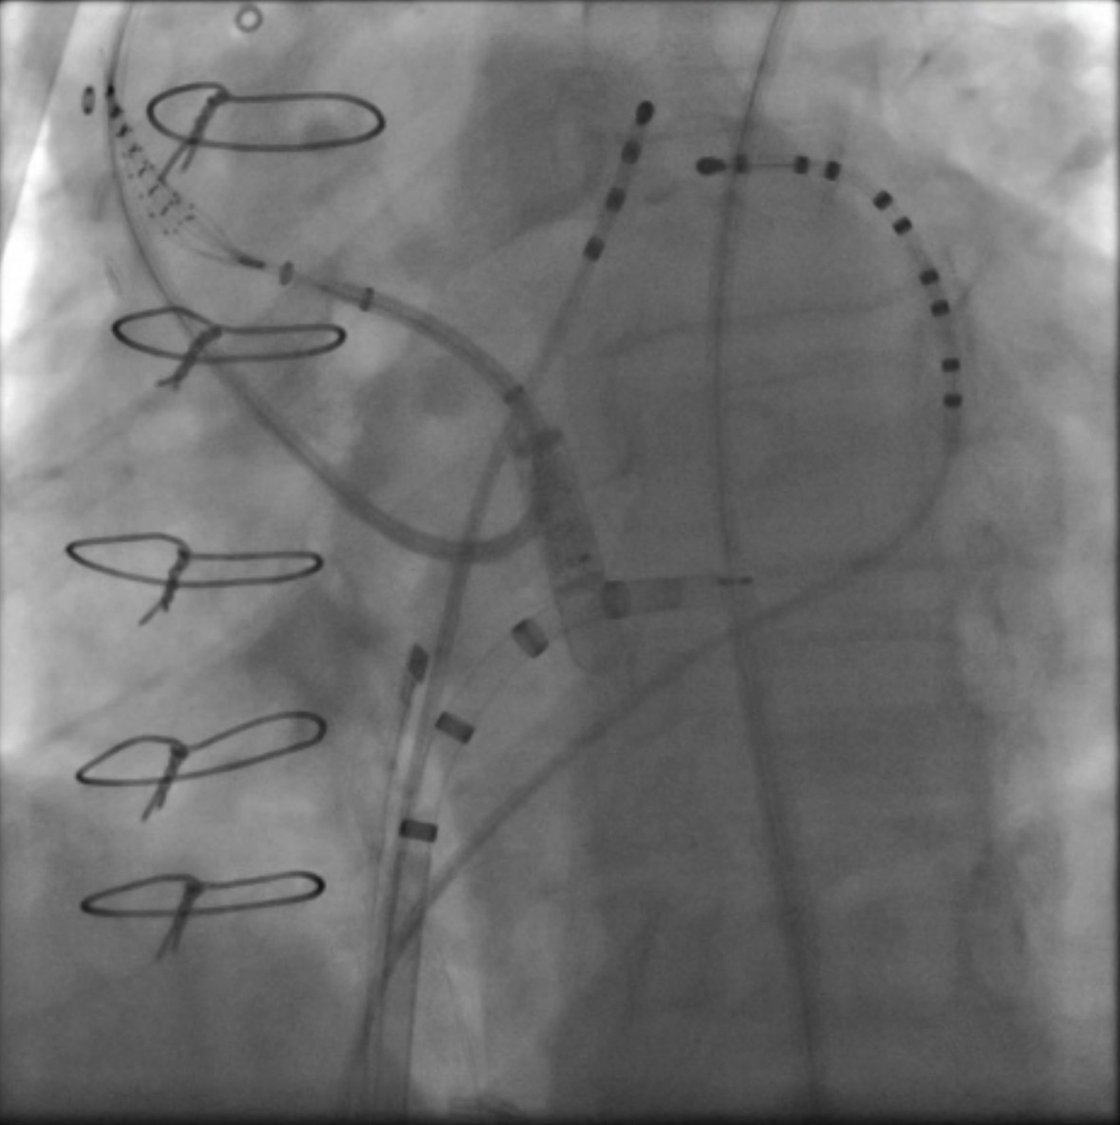

Patient with persistent AF and 3 prior AF ablations at an outside center. Congenital absence of the right SVC with massive PLSVC -- no prior ablation in the PLSVC. #EPPeeps What is your approach to ablation of PLSVC? @ReddyEPS @DrGregMichaud @jaymontgomery44 @ValayParikhMD